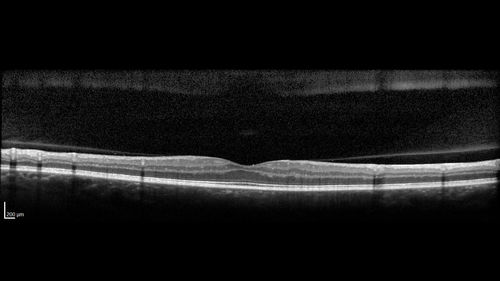

PDR and Vitreous Hemorrhage - High Risk Left Eye - Low Risk Right Eye

50 year old man with type I diabetes mellitus for 26 years. New Vitreous Hemorrhage in the left eye. Both eyes have NVE. Both also have foveal hypoplasia

Vitreous Hemorrhage and Proliferative Diabetic Retinopathy - Low risk right eye - High Risk Left Eye - Also Fovea Plana